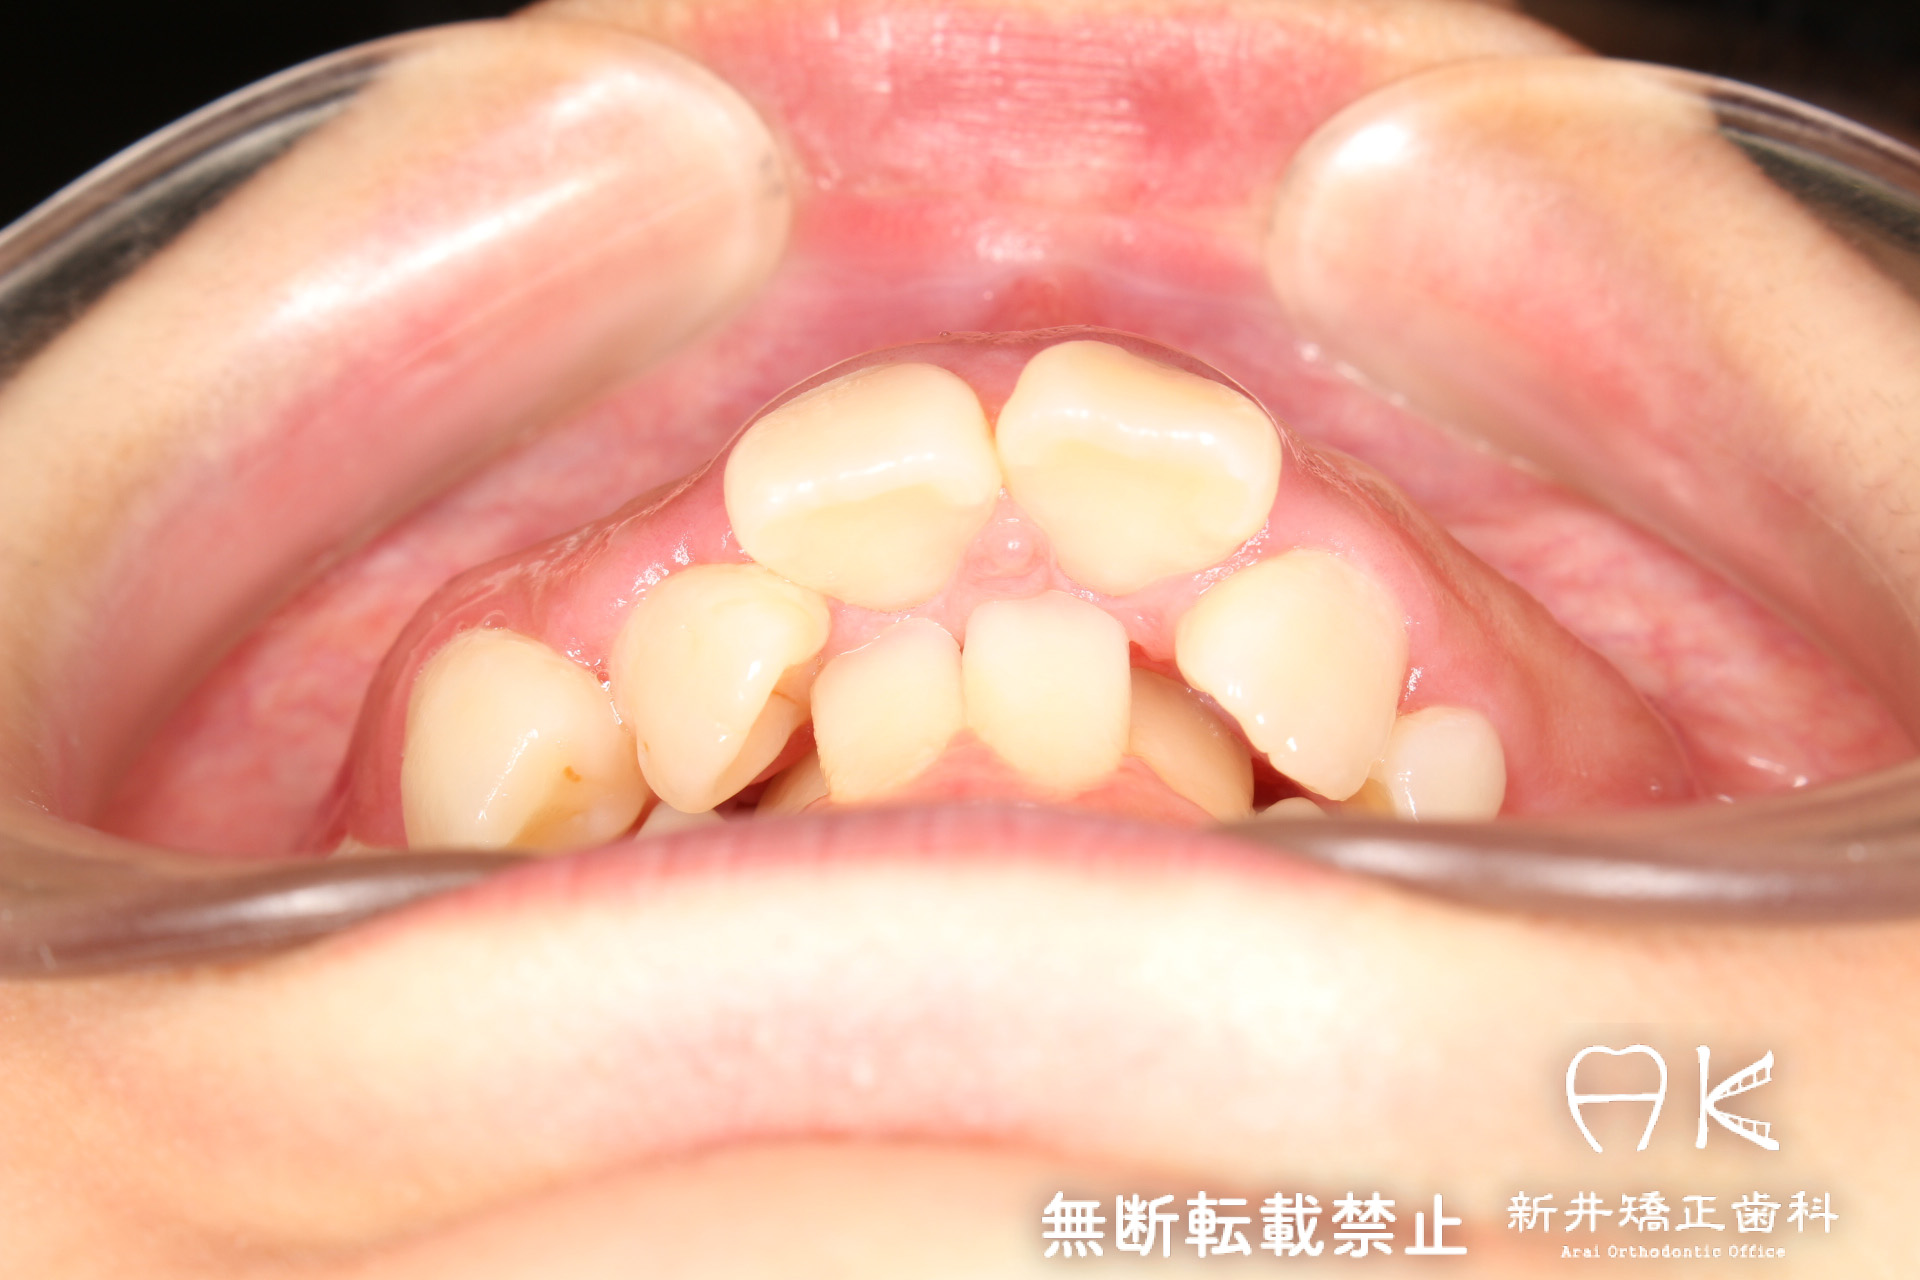

| 治療前 | 骨格的には受け口の患者さんですが、上顎前歯の唇側傾斜が大きく、患者さんとしては出っ歯だと思われていたパターンです。 元々口元の突出感はほとんどなかったため、歯を抜かずに上下顎ともに歯列を後方に移動させることにより主訴を改善させることとしました。 |